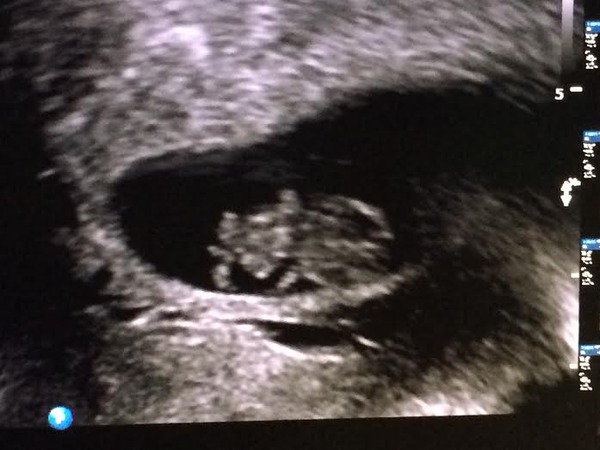

This is my little one

Ooooo, Isla! You're having a turtle! Mine was a chicken nugget last week and this week it looked like one of those weird alien-headed whales. Last wk it measured 18mm and this wk 27. It was waving its stubs! Another scan next Wednesday...